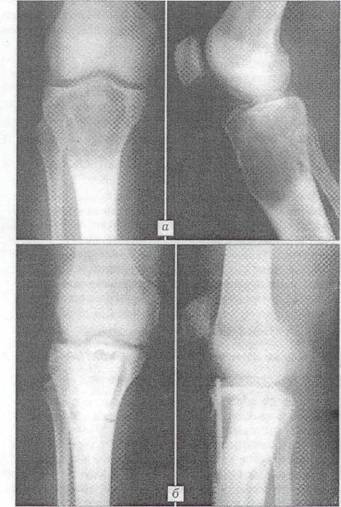

Анализ рентгенограмм показал, что через 1 мес. после хирургических вмешательств картина неоднороной "глыбчатой" структуры в местах заполнения дефектов "Остеоматриксом" или в пространствах между его гранулами и аллоимплантатами, выявлявшаяся сразу после опрерации, полностью исчезала. Рентгеновская ткань была практически однородной и имела умеренныю плотность (рис.1). Через 3 мес. в большинстве случаев (66%), я через 6 мес. у всех больных места, куда помещался "Остеоматрикс", по плотности рентгеновского изображения были неотличимы от окружающей губчатой костной ткани (рис. 2). Признаки перестройки замороженных кортикальных аллоимплантатов, применявшихся совместно с гранулами "Остеоматрикса", во все сроки наблюдения были минимальными (рис. 3), тогда как поверхностно-деминерализованные кортикальные аллотрансплантаты к 6-му месяцу частично инкорпорировались в материнское костное ложе (рис. 4).

Рис.2 Рентгенограмма больной Т. 41 года.

Диагноз: воспалительный процесс в области внутреннего надмыщелка правой бедренной кости. а - после отбрытой биопсии; б - через 3 мес. после операции с пластикой дефекта "Остеоматрисом".

Рис.4 Рентгенограммы больной С. 21 года.

Диагноз: гигантоклеточная опухоль большеберцовой кости. а - до операции; б - через 5 мес. после операции с пластикой дефекта "Остеоматриксом" и "Перфоостом".